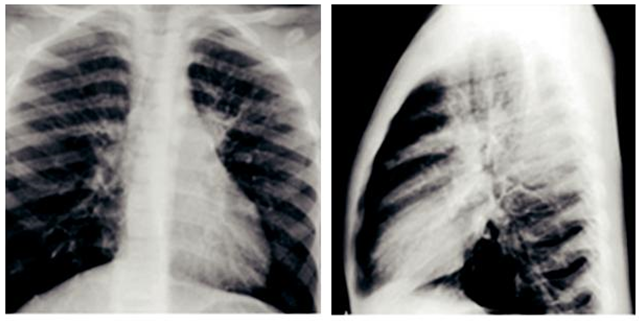

Radiografía de tórax (figuras 1A y 1B)

Presencia de infiltrado alveolar en ambos campos pulmonares.

Hilios pulmonares congestivos.

Incremento de la trama bronco vascular bilateral.

Cardiomegalia ligera.